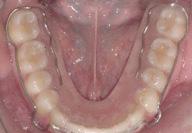

En la fotografía lateral derecha en la Figura 2 se observa la clase I molar y canina, en la Figura 3 línea media superior dental no coincidente con la media facial, en la Figura 4 clase II molar y canina, en la Figura 5 y 6 una forma de la arcada ovoide superior e inferior.

Figura 2. Intraoral derecha Figura 3. Intraoral de frente Figura 4. Intraoral izquierda Figura 5. Oclusal superior

El tiempo activo de tratamiento fue de 2 años y 11 meses, en la Figura 9 se observa la liberación del apiñamiento maxilar y mandibular, corrección de la mordida profunda, se obtuvo la clase I canina bilateral, la clase I molar bilateral, coincidencia de las líneas medias dentales y se logró

correcta intercuspidación, guía incisiva y guía canina.

Las formas de las arcadas se mantuvieron ovoideas al final del tratamiento (Figura 10), para la estabilidad y retención se indicó al paciente el uso de circunferencial super e inferior con pantalla vestibular y retenedores Vivera.

Figura 9. Intraorales finales Figura 10. Vista oclusal final